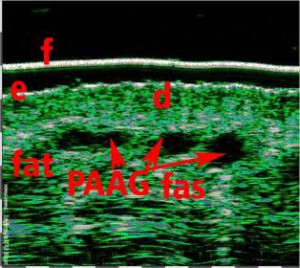

-Έγχυση Πληρωτικών Υλικών (Fillers)